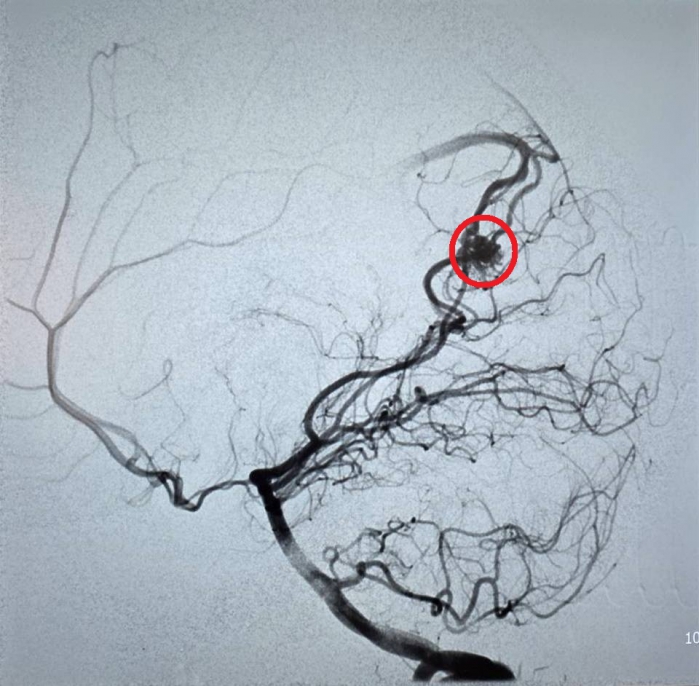

(特派員劉鳳瑩、陳明/苗栗報導)23歲的周小姐正值青春年華,日前卻在毫無預兆下感到一陣劇烈頭痛,隨即伴隨嚴重的頭暈與嘔吐感,家屬見狀趕緊將她送往大千綜合醫院急診。經腦部電腦斷層掃描,醫師赫然發現其左側腦部有出血跡象,且出血位置極其不尋常。醫療團隊隨即展開精密檢查,證實為罕見的「顱內動靜脈畸形」引發出血。所幸在神經放射科康靜維醫師及時進行微創血管內栓塞治療後,順利止住出血,病人症狀明顯改善,成功化解一場腦內危機。

康靜維醫師表示,顱內動靜脈畸形若未及時診斷與治療,每年約有1%至3%的出血風險。目前的治療技術已相當多元且成熟,主要包含:

1.微創血管內栓塞:透過導管進入血管,精準封堵畸形處。